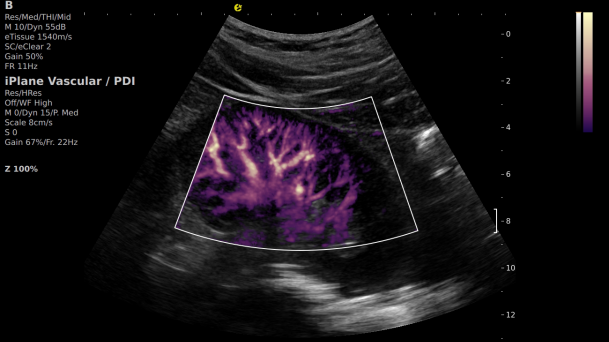

在肾移植领域,医生最怕的不是手术刀下的惊心动魄,而是那些手术后肉眼看不见的危机——急性排斥反应导致的血小板聚集形成的微血栓、毛细血管网损伤等...这些“隐形杀手”曾让无数移植肾在悄无声息中衰竭。而百乐博平台医疗(ESI)的iPlane Vascular平面波超微细血流显像技术,正是为破解这一难题而生。

1) 基于OmniSound?平面波超快速平台,超声信号采集帧频提高了200倍(25000Hz)。

2) 可检测20-50μm级细小血管低速血流信号,能看清头发丝1/2粗细的微血管;

3) 通过血管指数(VI)定量评估局部血管密度,以定量化数据实时监测血流灌注情况,预判肾功能恢复情况;

超微视血流显像显示肾脏五级血管

肾脏的灌注评估,RI/VI量化数据

超微视血流显像评估肾移植术后灌注情况

这一项无创、无辐射操作简便且无需造影剂的黑科技,相当于用"高速摄像机"记录血液细胞的运动轨迹,让血管并发症"无处遁形。

从术前评估到术中到术后,再到终身监护,当20-50μm级的超微血流信号在屏幕上跳动,我们看到的不仅是技术的精进,更是生命的律动。iPlane Vascular正在重新定义肾移植监护的标准——让医生拥有了"显微视力",让每一个微小血管的异常都无所遁形,让每一次免疫排斥的萌芽都被及时扼制。